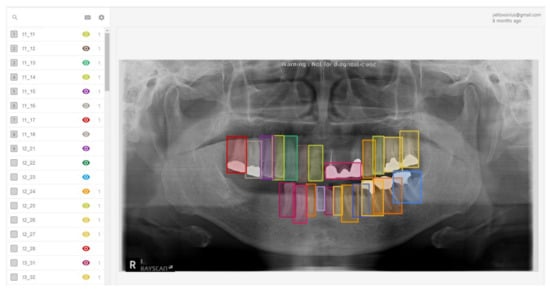

A total of 303 panoramic patient data were collected from the Medipartner Dental Network Hospital after obtaining patient agreements. Each image was anonymized and converted into a 1600 pixel × 900 pixel image in JPG format. Three dentists labeled each panoramic tooth image, using Label Box as the labeling tool. Figure 4 shows the labeling results on an image from the Label Box tool used by the dentists. Only labeled dental implants with fixtures were included in the data set because we did not have enough abutments and prostheses images on the dental panorama images.

Figure 4. Labeling tool used to generate training and test sets.